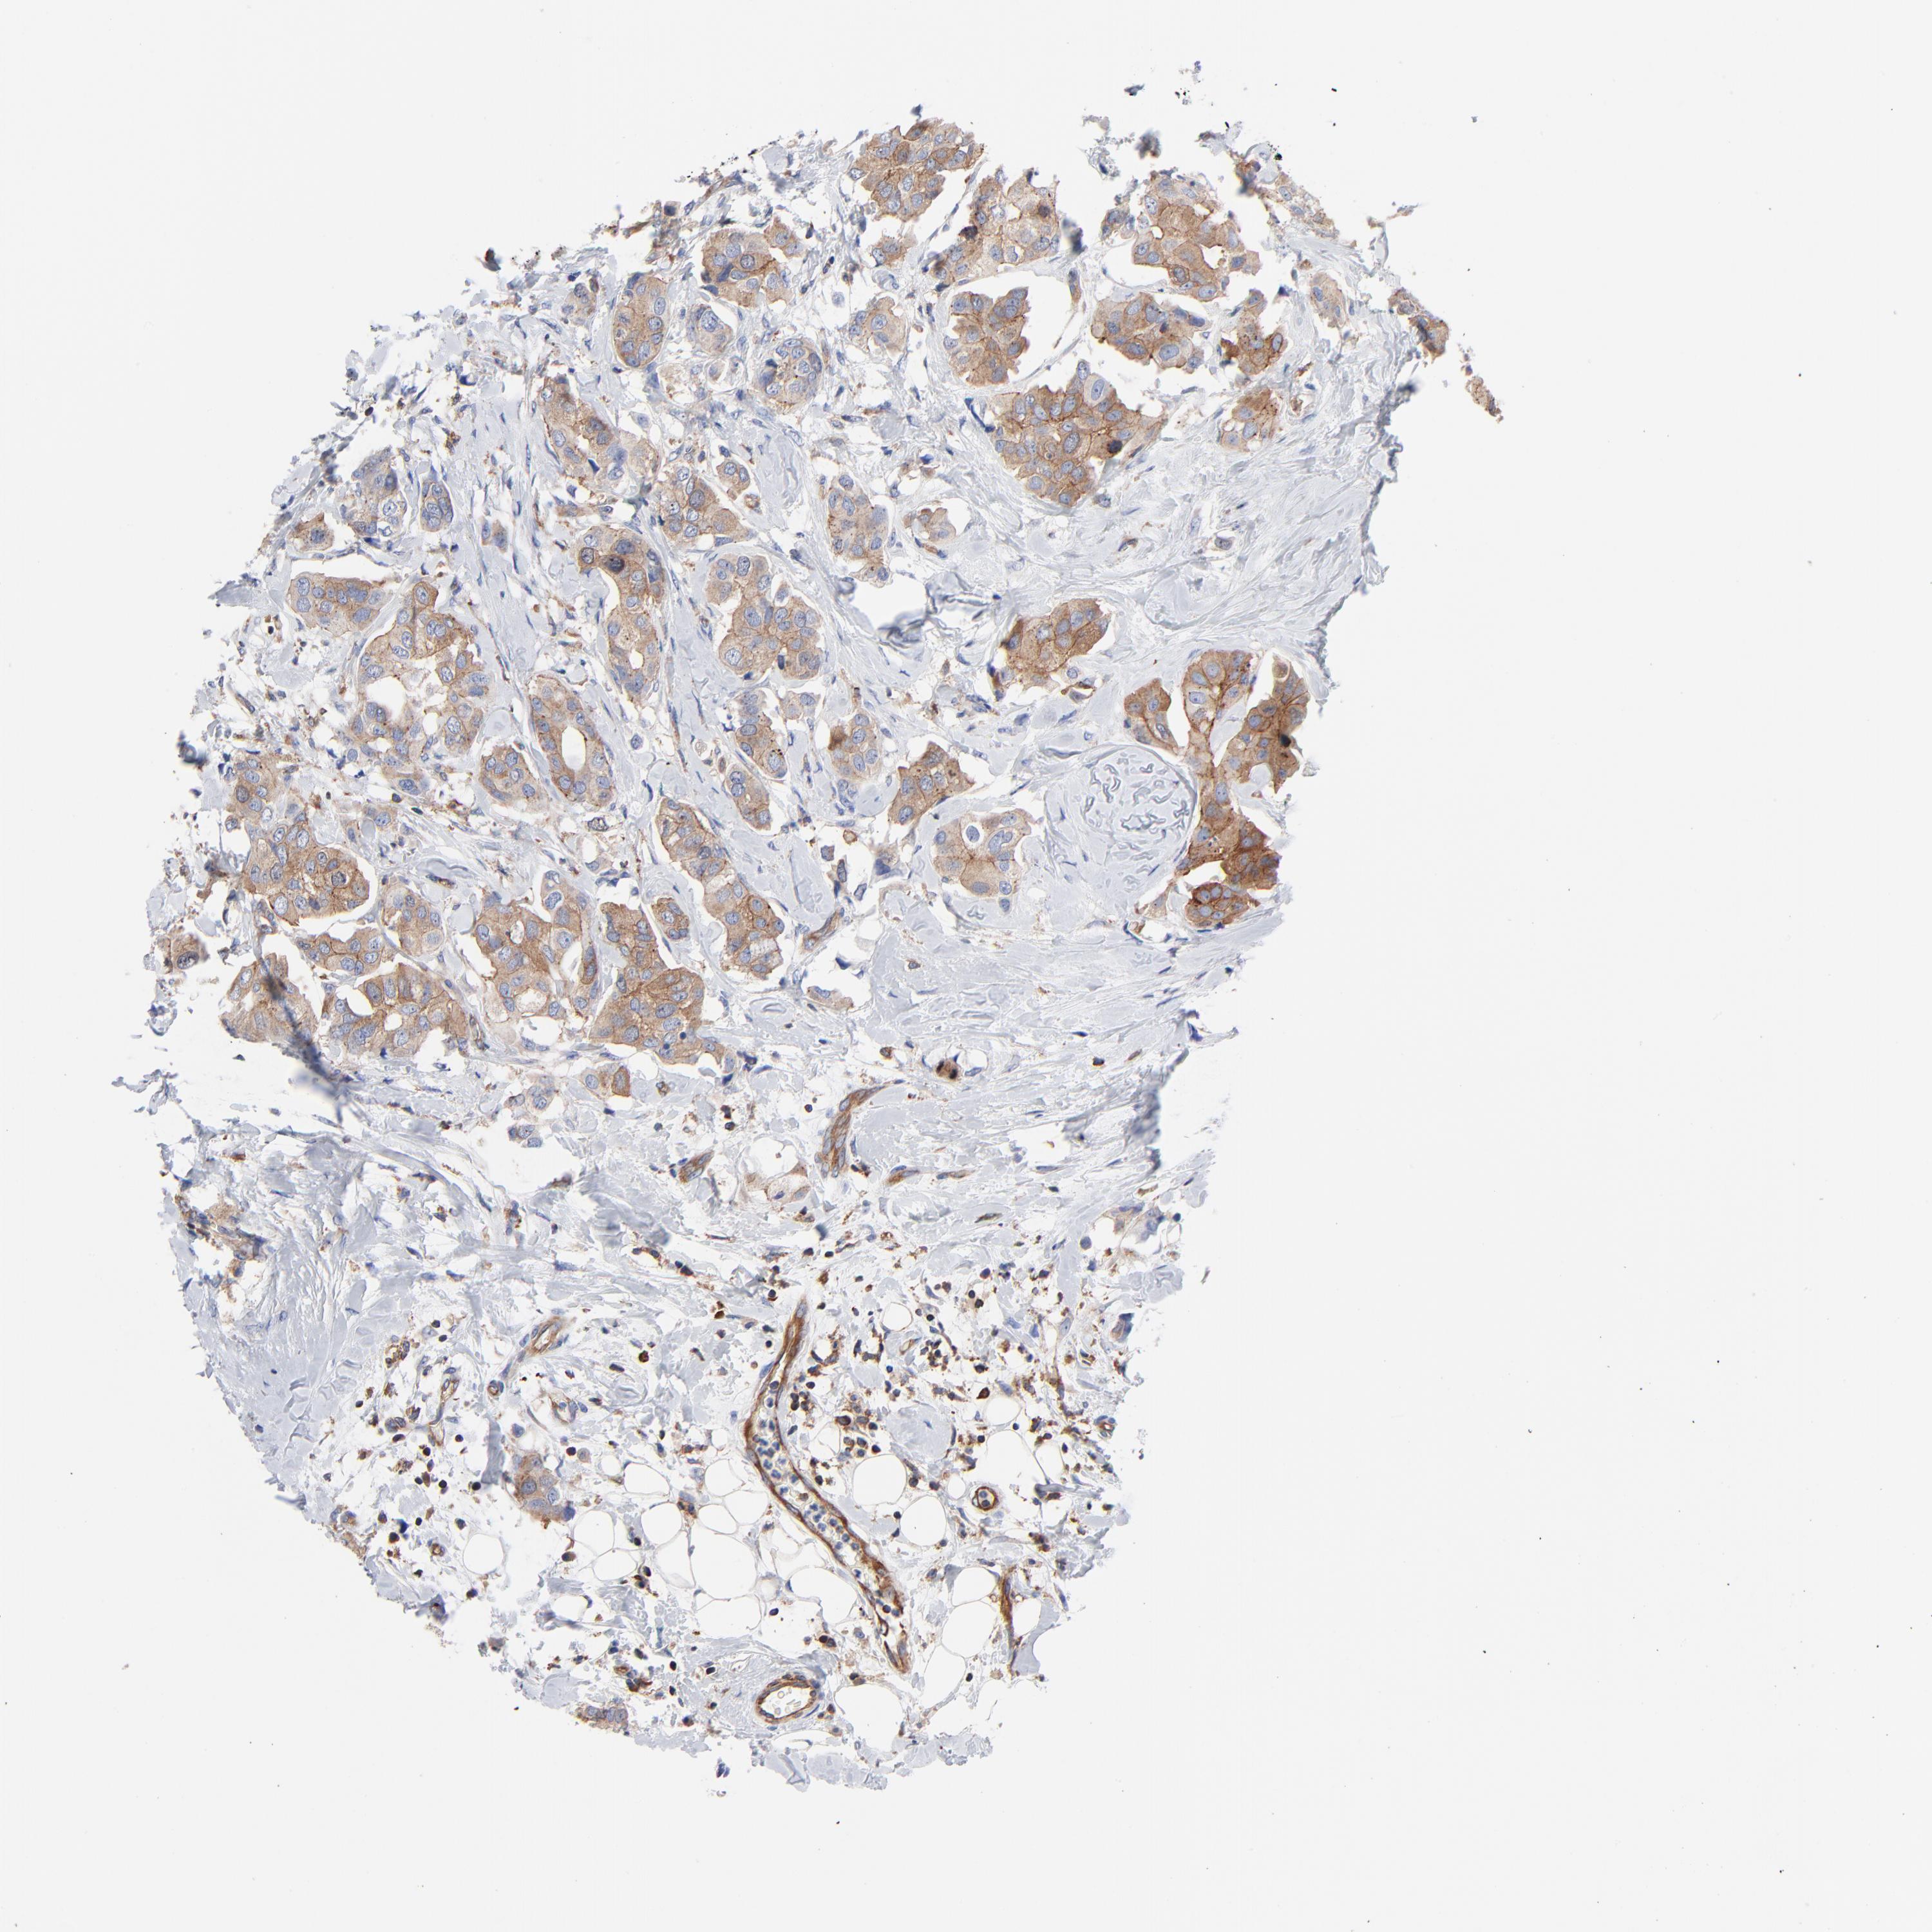

BRCA TCGA BRCA VALIDATION PROTEIN EXPRESSION

ANTIBODIES

AND

VALIDATION